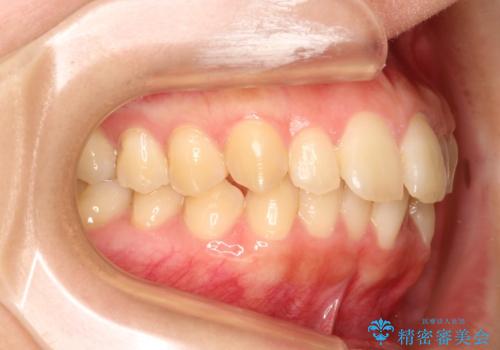

出ている前歯をインビザラインにて引っ込める

- 前歯が少し前に出ているのが気になるとのことで来院されました。

インビザラインにて上顎の歯を全体的に後方に移動させて前歯を引っ込める計画としました。

使用時間を守っていただけたので、比較的スムーズに矯正を終了することができました。